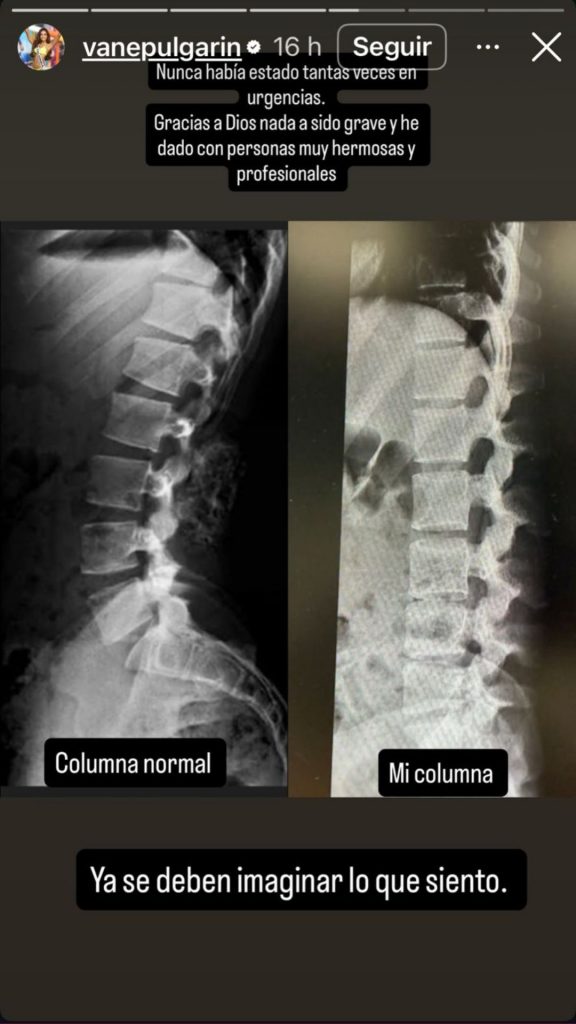

Según explicó en las historias que acompañaron la publicación, todo comenzó cuando sintió un dolor muy intenso en la columna que fue aumentando con el paso de las horas. La molestia llegó a ser tan fuerte que tuvo que buscar atención médica de urgencia, situación que la llevó a ser evaluada por varios especialistas en salud.

Los profesionales consideraron necesario realizar diferentes exámenes para determinar el origen del dolor y garantizar que recibiera el tratamiento adecuado, lo que justificó su presencia en el centro hospitalario.

“Nunca había estado tantas veces en urgencias. Gracias a Dios nada ha sido grave y he dado con personas muy hermosas. No se preocupen, hoy ya puedo moverme mucho más”, mencionó Miss Colombia.